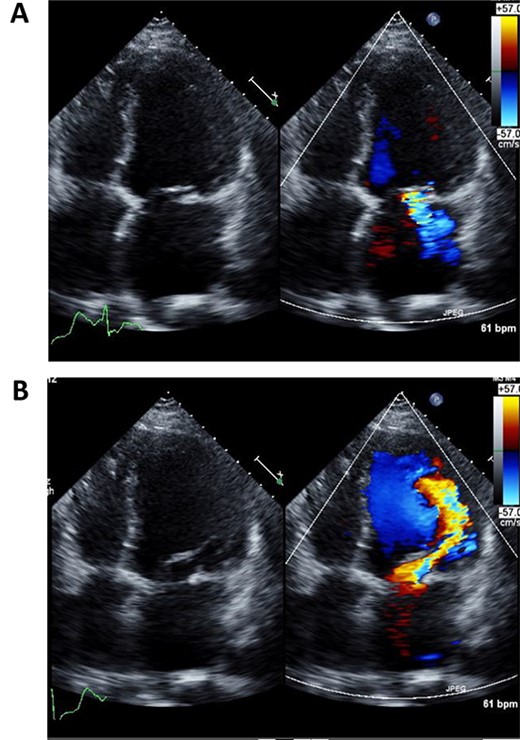

A 50-year-old male who had undergone MV repair 14 years ago due to traumatic mitral valve regurgitation was presented to our department due to heart failure with New York Heart Association (NYHA) III classification. Chest X-ray showed moderate cardiomegaly, and electrocardiogram showed atrial fibrillation with controlled heart rate (Fig. 1A and B). Transthoracic echocardiogram showed moderate MR with severely impaired bi-ventricular function; left ventricular ejection fraction of 20%, (Fig. 2A and B). Coronary angiography showed no significant stenosis. Although indication for mitral valve surgery was marginal [2], surgical intervention was decided to prevent further deterioration of bi-ventricular function.

Preoperative echocardiography of left ventricle in systolic (A) and diastolic (B) phases.